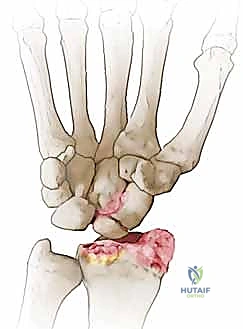

متلازمة SNAC (Scaphoid Nonunion Advanced Collapse) هي حالة تدهور تدريجي ومأساوي لمفصل الرسغ. تبدأ القصة بكسر في العظم الزورقي (غالباً بسبب السقوط على يد ممدودة). إذا لم يتم تشخيص هذا الكسر أو لم يلتئم بشكل صحيح، فإن العظم الزورقي ينقسم إلى قطعتين تتحركان بشكل غير طبيعي ومستقل عن بعضهما البعض.

هذه الحركة غير الطبيعية تخلق احتكاكاً مستمراً (Micro-trauma) مع العظام المجاورة، وتحديداً عظم الكعبرة (Radius). بمرور الوقت (أشهر أو سنوات)، يؤدي هذا الاحتكاك إلى تآكل الغضاريف الناعمة التي تغطي العظام، مما يسبب خشونة مفصلية شديدة (Osteoarthritis).

- المرحلة الأولى (Stage I): خشونة وتآكل في المفصل بين القطب البعيد للعظم الزورقي وعظم الكعبرة (الناتئ الإبري الكعبري).

- المرحلة الثانية (Stage II): يمتد التآكل والخشونة ليشمل المفصل الزورقي الكبير (Scaphocapitate joint).

- المرحلة الثالثة (Stage III): تدهور كامل يشمل المفصل بين عظم الهلالي والعظم الكبير (Capitolunate joint)، مع انهيار كامل لهيكل الرسغ.

تُعد عملية استئصال القطب البعيد للعظم الزورقي (Excision of the Distal Pole of the Scaphoid) حلاً جراحياً ذكياً ومبتكراً. الفكرة الميكانيكية وراء هذه الجراحة هي: "إذا كان القطب البعيد للعظم الزورقي هو الذي يحتك بعظم الكعبرة ويسبب الألم والخشونة، فلنقم بإزالته مع الحفاظ على باقي هياكل الرسغ".

- الاستئصال الدقيق: باستخدام أدوات جراحية ميكروسكوبية دقيقة، يتم استئصال حوالي 3 إلى 4 مليمترات من القطب البعيد للعظم الزورقي. هذه الكمية كافية لمنع الاحتكاك مع عظم الكعبرة، وفي نفس الوقت تحافظ على استقرار الأربطة.